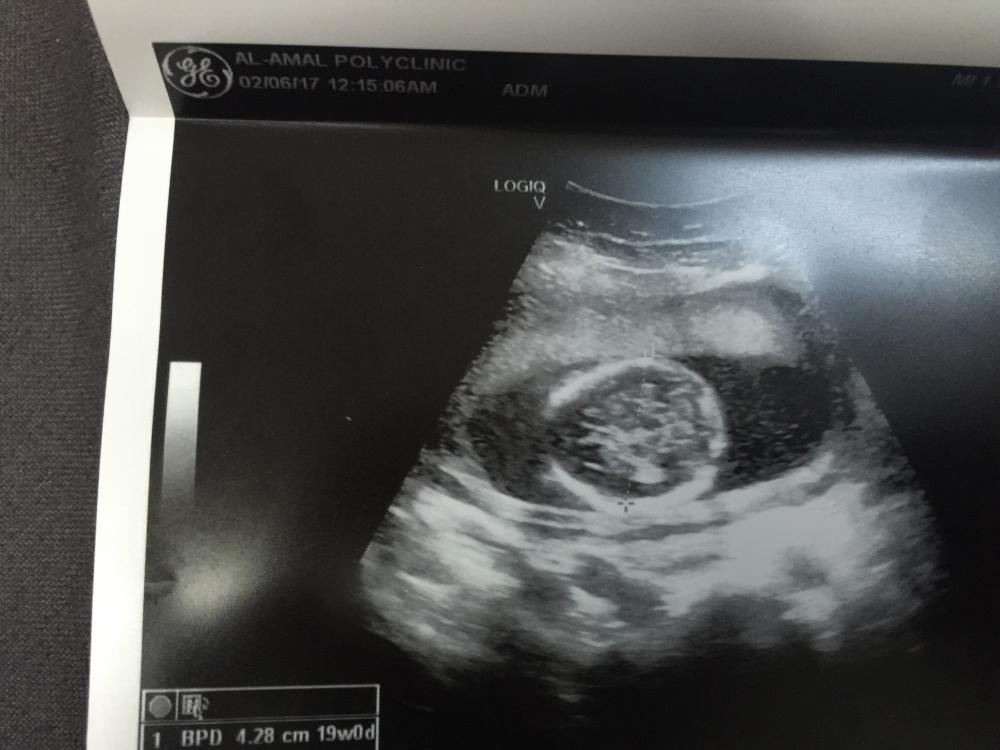

السلام عليكم اللي عندهم خبرة ب السونار